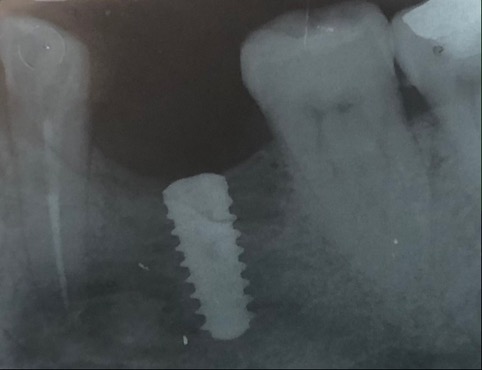

Un impianto dentale o fixture è un corpo in titanio, totalmente biocompatibile, che viene posizionato nella mascella o mandibola con lo scopo di sostituire la radice di un dente naturale perso. Su di esso viene successivamente o immediatamente quando possibile (carico immediato) fissata la protesi ovvero la corona del dente restituendo funzione ed estetica.

Con l’implantologia oggi è possibile sostituire un solo dente come un’intera arcata anche in casi di deficit ossei grazie alla GBR (rigenerazione ossea guidata) che ci permette di intervenire quando la disponibilità ossea iniziale del paziente non sarebbe sufficiente.